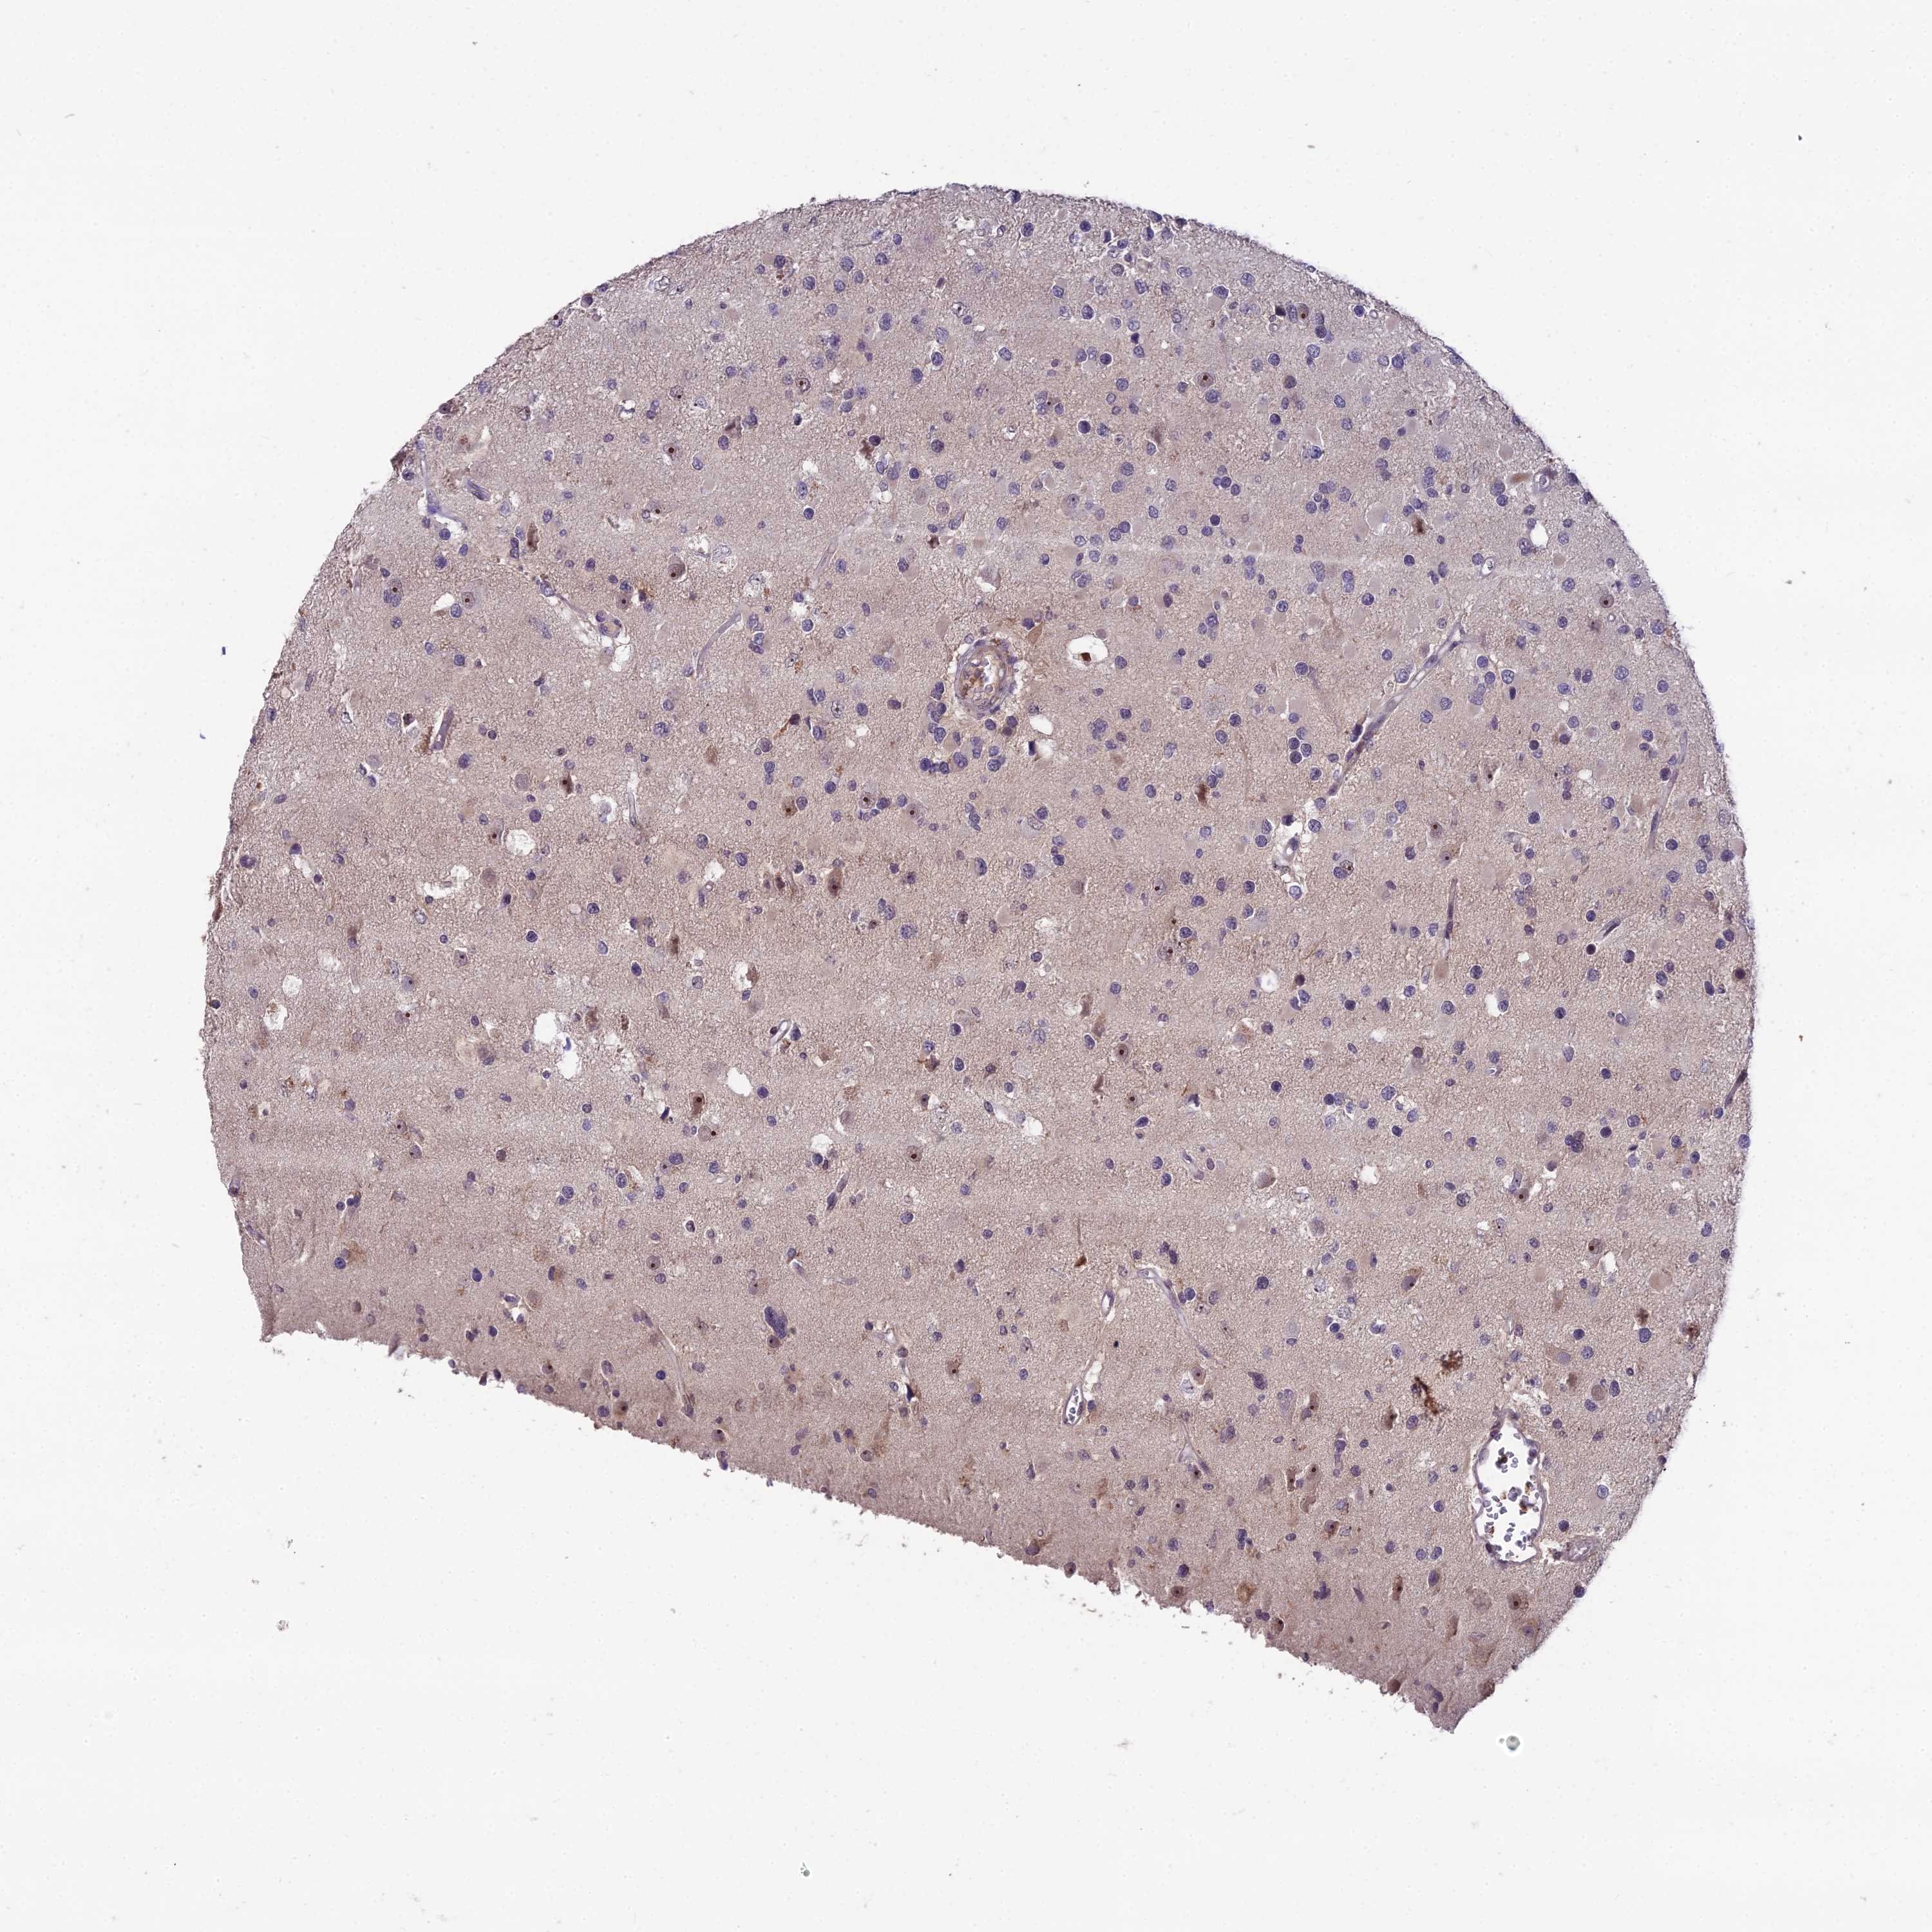

GLIOMA - Protein expressioni

A mouse-over function shows sample information and annotation data. Click on an image to view it in a full screen mode. Samples can be filtered based on level of antibody staining by selecting one or several of the following categories: high, medium, low and not detected. The assay and annotation is described here.

Note that samples used for immunohistochemistry by the Human Protein Atlas do not correspond to samples in the TCGA dataset.

Antibody stainingi

Antibody staining in the annotated cell types in the current human tissue is reported as not detected, low, medium, or high, based on conventional immunohistochemistry profiling in selected tissues. This score is based on the combination of the staining intensity and fraction of stained cells.

Each image is clickable and will lead to virtual microscopy that enables deeper exploration of all samples and also displays staining intensity scores, fraction scores and subcellular localization as well as patient and tissue information for each sample.

Antibody HPA043973

Staining

High

Medium

Low

Not detected

Intensity

Strong

Moderate

Weak

Negative

Quantity

>75%

75%-25%

<25%

None

Location

Nuclear

Cytoplasmic/membranous

Cytoplasmic/membranous,nuclear

Glioma, malignant, High grade

Glioma, malignant, Low grade